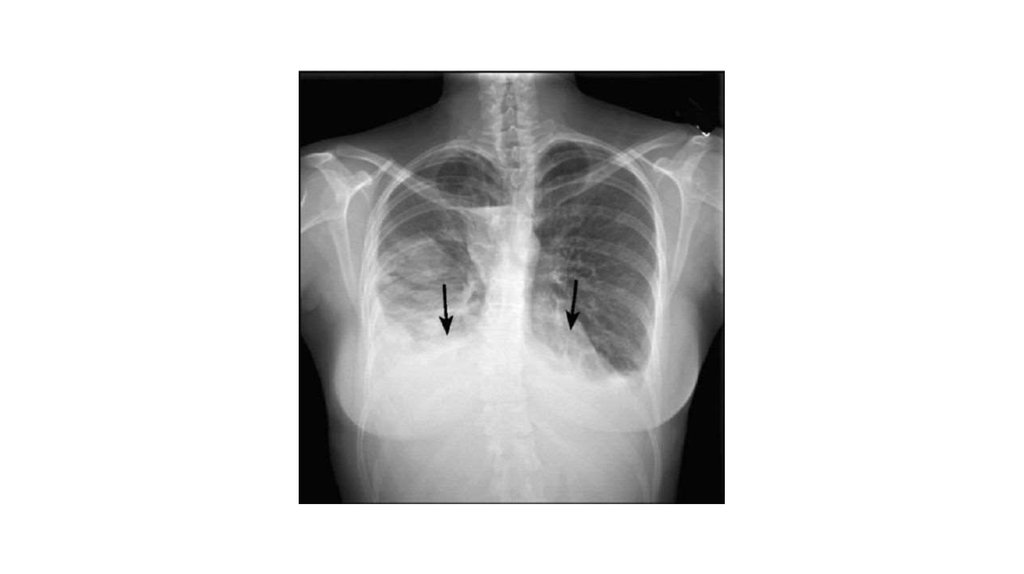

• Рентгенограмма грудной клетки, прямая проекция. Двусторонний

плеврит. Видны вогнутые уровни жидкости с двух сторон

(стрелки)